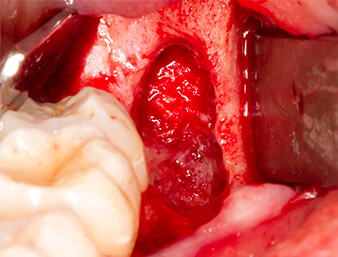

En la imagen en 3D (tomografía volumétrica digital) se constató que el resto radicular se encontraba muy desplazado en sentido distocaudal en la transición situada entre la porción horizontal y la ascendente del maxilar inferior (figura 2).

TVD transversal

Imagen 2: Representación de una TVD transversal del resto radicular en el espacio retromolar.